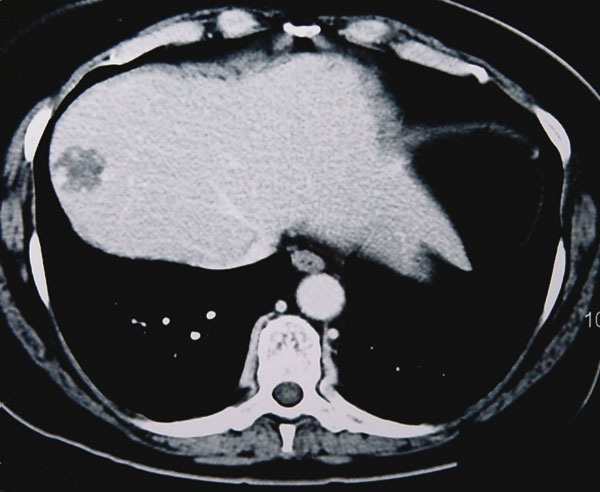

La Revue du Praticien - Jacques Belghiti Prise de contraste persistant à la phase tardive (motte périphérique).